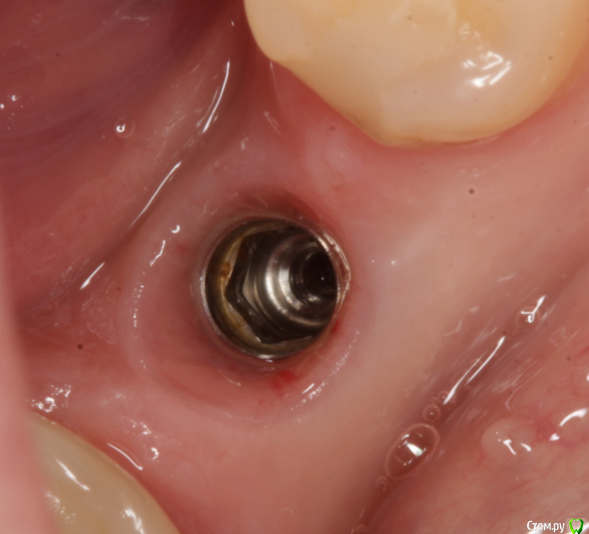

andrey75 Опубликовано 4 сентября, 2015 Поделиться Опубликовано 4 сентября, 2015 Пришла пациентка с просьбой запротезировать. Подскажите что за система и где взять на нее запчасти.Заранее Всем спасибо! Ссылка на комментарий

Bier Опубликовано 4 сентября, 2015 Поделиться Опубликовано 4 сентября, 2015 шестигранник на израиль похож 1 Ссылка на комментарий

diesel87 Опубликовано 4 сентября, 2015 Поделиться Опубликовано 4 сентября, 2015 Уверен что это двухэтапный корневидный имплантат с шестигранником ! 3 Ссылка на комментарий

Bier Опубликовано 4 сентября, 2015 Поделиться Опубликовано 4 сентября, 2015 Вангую, что это альфа-био ) 2 Ссылка на комментарий

Доктор Добрых Дел Опубликовано 4 сентября, 2015 Поделиться Опубликовано 4 сентября, 2015 (изменено) Думаю это xive.99% Изменено 4 сентября, 2015 пользователем Доктор Добрых Дел Ссылка на комментарий

АнтонТЛТ Опубликовано 4 сентября, 2015 Поделиться Опубликовано 4 сентября, 2015 Вангую, что это альфа-био )Неа))) у альфы от края имплантата к шестиграннику плавный переход, а тут со ступенькой Ссылка на комментарий

АнтонТЛТ Опубликовано 4 сентября, 2015 Поделиться Опубликовано 4 сентября, 2015 Думаю это xive.99%Тоже к этому склоняюсь)) Ссылка на комментарий

Доктор Добрых Дел Опубликовано 5 сентября, 2015 Поделиться Опубликовано 5 сентября, 2015 (изменено) Вот с сайта "апекс" описание системы и внешний вид платформы. Я их несколько раз ставил. Очень похоже что это он.1000% онДиллер XiVE в России SIMCO в Москве. Думаю у них можно заказать. В Краснодаре Ксайвом работают в сети "Интан" (Питерская сеть клиник уже до Краснодара разрослась) может ещё кто-то. Возможно через них можно попробовать. Изменено 5 сентября, 2015 пользователем Доктор Добрых Дел 1 Ссылка на комментарий